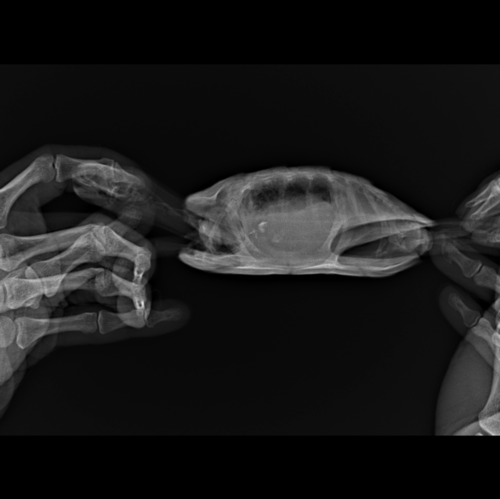

Анастасия- Ваше имя: Анастасия Локация: Ереван Опубликовано: 18 января 2022 Автор Опубликовано: 18 января 2022 Вот такой у нас сегодняшний рентген, врач сказала продолжать антибиотик, прийти на повторный анализ крови а вот это рентген от 4 января перед курсом антибиотиков и уколами Элеовита:

Консультанты moth Ваше имя: Мария Локация: Москва Опубликовано: 18 января 2022 Консультанты Опубликовано: 18 января 2022 @Анастасия- по лёгким тут явно лучше на сколько я могу читать снимки - по-моему там есть скопление газов, что и могло приводить к тому, что Вы описывали. Врач ничего не говорила про это?

Анастасия- Ваше имя: Анастасия Локация: Ереван Опубликовано: 18 января 2022 Автор Опубликовано: 18 января 2022 @moth врач сказала, что в кишечнике много газов, пока ждать что будет дальше, и что кусочков инородных больше не видно. Сегодня делали у врача укол Элеовита, а вечером уже я делала антибиотик, и черепашка обмочилась очень желтым, такого яркого раньше не было - наверное из-за витаминов? Сегодня черепашка довольно подвижная, то плавает, то на островке сидит, но кушать пока отказывается

Консультанты moth Ваше имя: Мария Локация: Москва Опубликовано: 18 января 2022 Консультанты Опубликовано: 18 января 2022 @Анастасия- да, цвет из-за витаминов. Ну будем надеяться, что всё будет хорошо. Газы сильно сдавливают лёгкие и другие органы, черепахе больно и не комфортно, поэтому так себя вела.